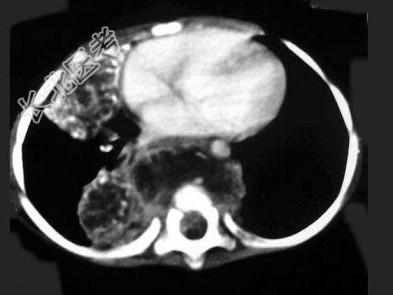

- 单项选择题男,8岁, 咳嗽、咳脓痰,背部肿痛。结合图像, 最可能的诊断是 ( )

E、脊椎结核